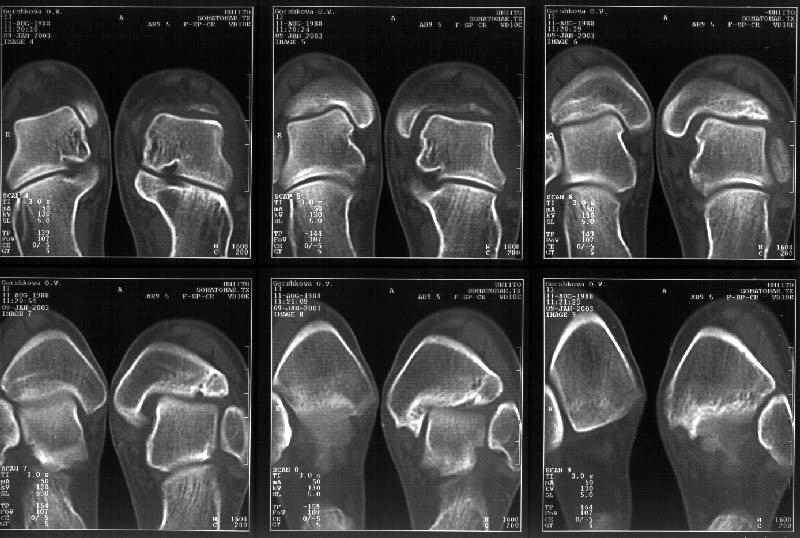

Здесь 4 среза, начиная от основания лодыжки и проксимальнее. Где, по Вашему мнению, проходит линия перелома, отделяющая переднюю часть внутренней лодыжки от большеберцовой кости? Заранее спасибо.

Сегодня пациентке сделали сравнительную КТ. А ксиальные и Фронтальные срезы приложены. Ваше мнение?

Фронтальные